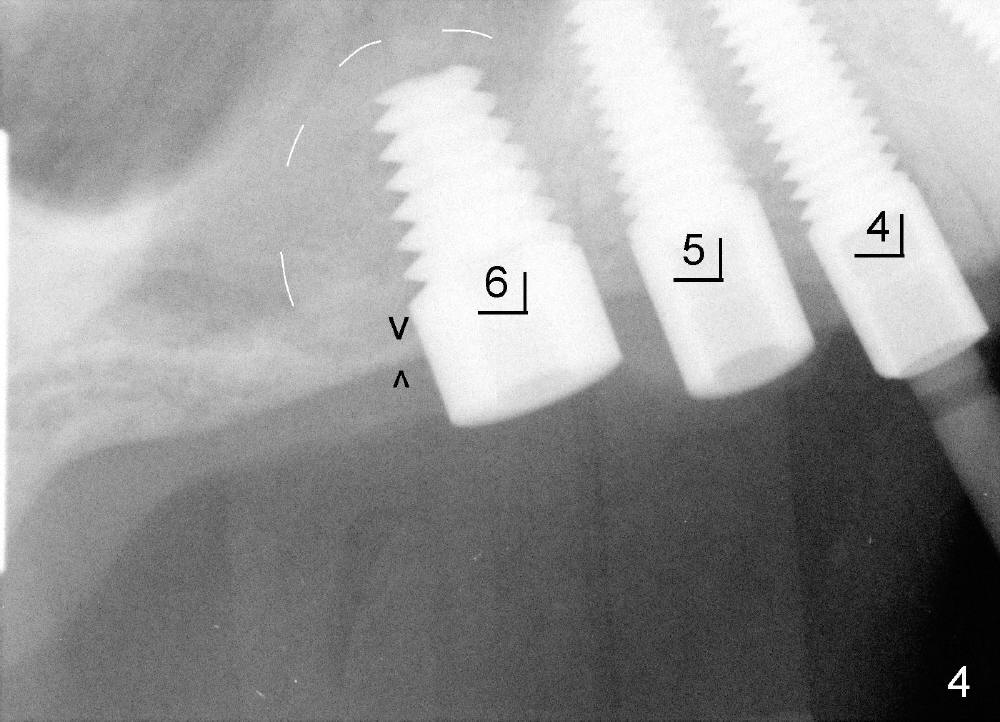

五十来岁吴先生牙周病严重(图一),尤其右上4,5,左上6,最后拔除(图二:远中面观),可见口腔卫生差。先做局部托牙,三年后又失去几个下牙,终于同意植牙。主要困难是上颌窦很低,最好先做上颌窦植骨,但是他胆子特小,多做一个手术对他来说是很大精神创伤,所以壮着胆子先做左上6植牙(图五:7x11mm,torque > 60 Ncm),虽然远中底板不可观(图五箭头之间),但是植牙很牢靠。右侧上颌窦底板更薄,估计不做上颌窦植骨不行,给他吹风说需要做一个手术才能植牙,他竟然同意。但是突然他的托牙(framework removable partial denture)断裂了,断在金属部分(major connector: anterior and posterior bars),说明他咀嚼力如此大,技工室说激光焊接没有保证。我们不得不取消上颌窦植骨,因为它会延迟植牙五六个月,所以我们再次铤而走险在右上第一双尖牙(图三:4, 4x20mm,> 60 Ncm)和第一磨牙(6, 6x11mm,> 60 Ncm)植牙,一个月后在两者之间再植入一个(图四:5,4.5x14mm,> 60 Ncm)。尽管第一磨牙植牙远中骨板相当薄(图四箭头之间),但是它很紧,可能与上颌窦底板坚硬有关。在病人多次要求下,半个月后就装上基牙(图六:2,4,5,6),放置临时牙冠,后三者连在一起(好像牙桥,增加稳定性),这样病人可以正常吃饭。一周后,侧切牙临时牙冠脱落,病人回诊所重新粘固,而右上牙桥仍稳定。

虽然牙周病病人骨头高度损失,但是颊舌侧宽度仍正常,尽量使用直径大的植牙。总而言之,牙周病病人骨质并不差。